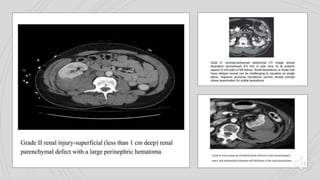

Grade I Grade II Grade III Grade IV Grade V

& renal parenchymal

lacerations are key terms

Lacerations are

superficial (<1cm) and

there is no urine leak